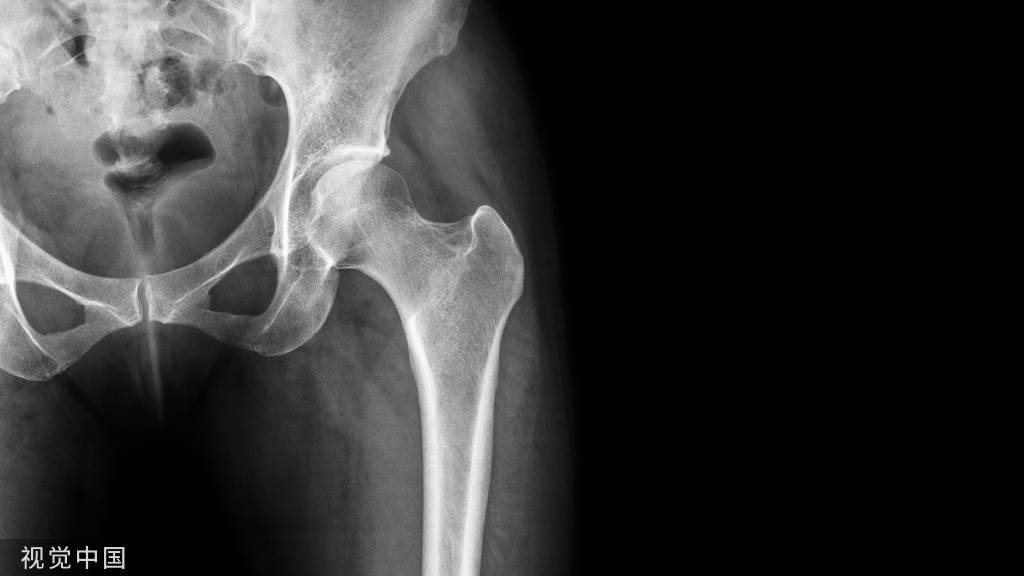

股骨远端骨折示例。沿股骨远端骨块作一中轴线,骨折线与中轴线相交,形成2锐角(Acute angles)。